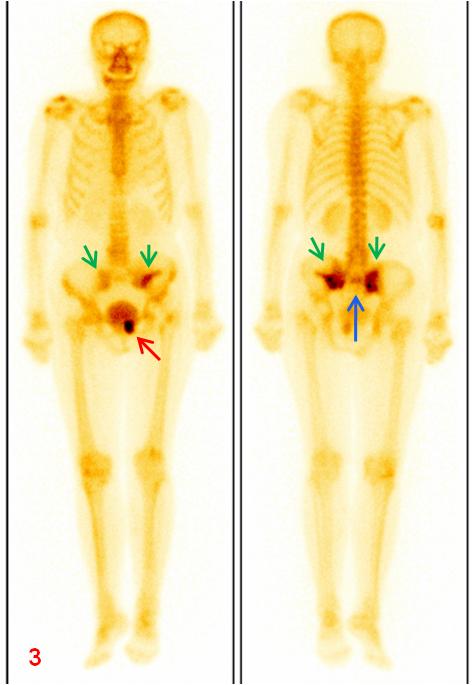

老年女性,1年前因直腸惡性腫瘤于外院行放射治療,此次常規(guī)復查平掃CT示骶骨及左側(cè)恥骨密度不均勻,左側(cè)恥骨骨質(zhì)斷裂;平掃MR示雙側(cè)骶骨翼、左側(cè)髂骨及左側(cè)恥骨異常信號(圖1、2);為進一步明確診斷行全身骨顯像ECT檢查(圖3)。

圖3全身骨顯像:雙側(cè)骶髂關(guān)節(jié)(綠箭)、骶骨(藍箭)及左側(cè)恥骨(紅箭)放射性異常濃聚。